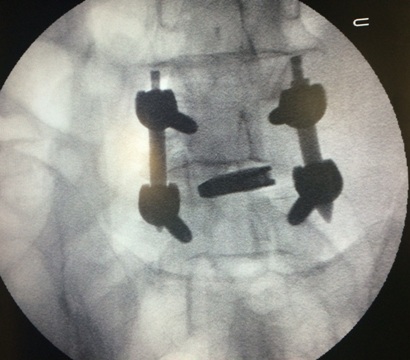

Image During Surgery